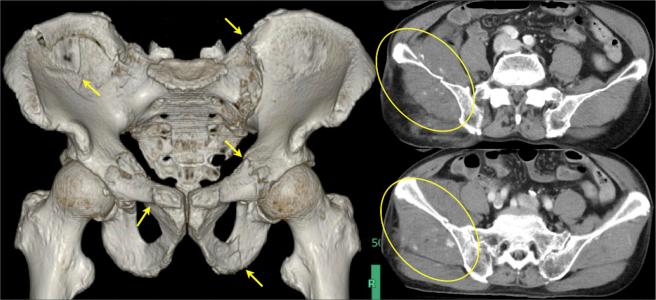

Visualized Efficacy of Andexanet Alfa in an Elderly Trauma Patient with an Unstable Pelvic Fracture.

JMA J. 2024 Jul 16;7(3):438-440. doi: 10.31662/jmaj.2024-0007. Epub 2024 Jun 3.

DOI:10.31662/jmaj.2024-0007

PMID:39114625

原文链接:https://pmc.ncbi.nlm.nih.gov/articles/PMC11301022/